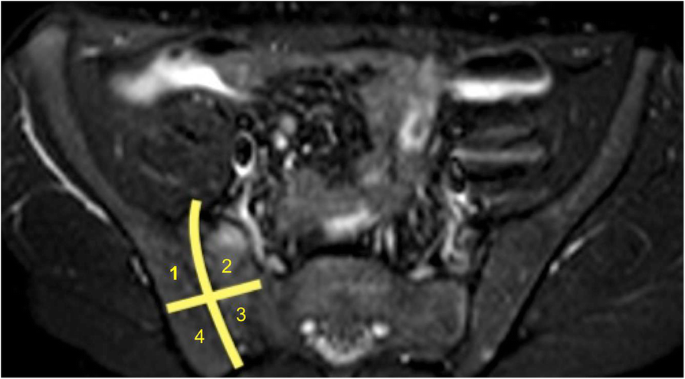

Image analysis

Two blinded observers with experience in pediatric and skeletal imaging (AP, MDM) independently evaluated the images. Before reading the MRE, a consensus about the definition of inflammatory lesions in SI joints was reached. MRI signs of sacroiliitis in adults are described by the ASAS criteria [22], but at the moment, no such definition of a positive MRI for sacroiliitis exists in children with juvenile spondyloarthritis [23]. For this reason, and for the retrospective nature of this study, where targeted sequences for SI joints analysis on MRE lacked, we decided to evaluate the presence of bone marrow edema (using T2W sequences with fat suppression, SPAIR), as a defining sign of sacroiliitis. In addition, the presence of diffusion restriction in Diffusion Weighted Imaging (DWI) or Diffusion Weighted Imaging with Background Suppression (DWIBS), and dynamic contrast enhancement were evaluated. Each SI joint was divided into 4 quadrants: upper iliac, lower iliac, upper sacral, and lower sacral (Fig. 1). Cases upon which there was a disagreement were reevaluated together by the two reviewing radiologists and a third radiologist (MB) with similar experience.